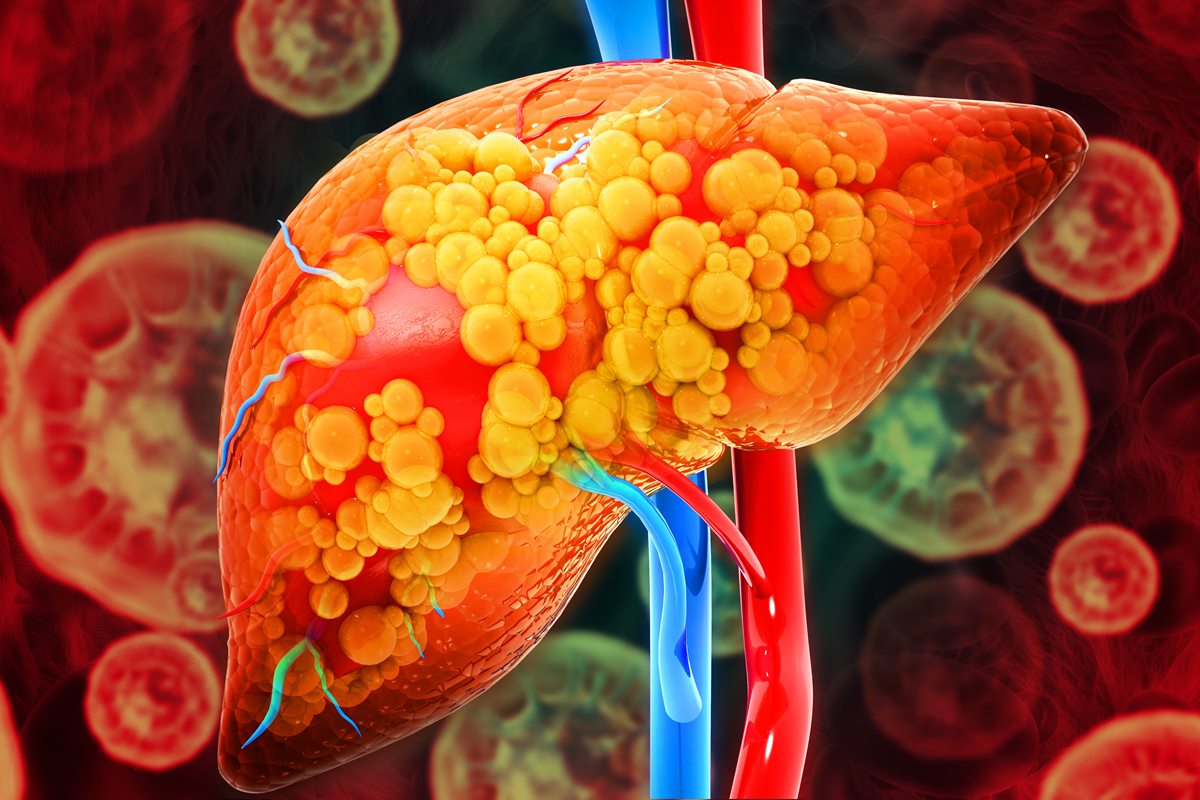

A condição de gordura no fígado acomete 30% da população mundial, segundo o artigo

Visão microscópica de células em fígado com gordura, a esteatose hepática